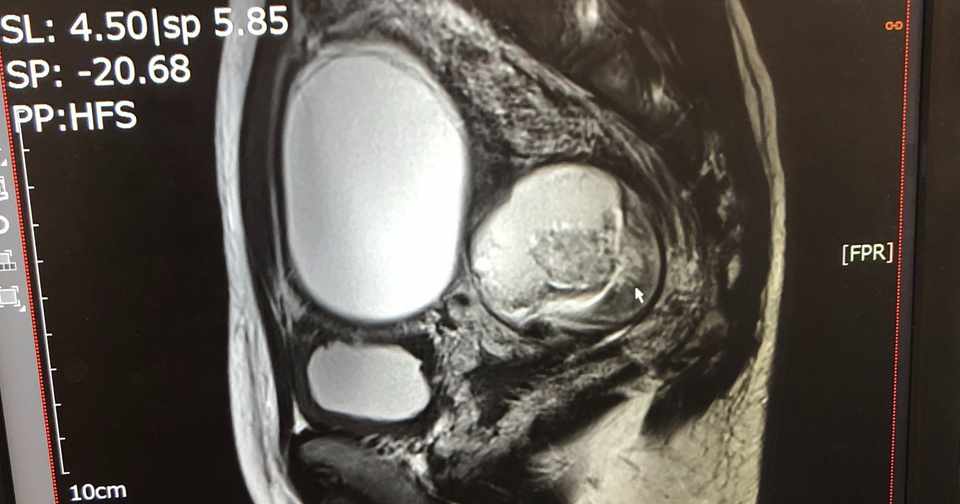

Ovarian Mature Cystic Teratoma Radiology Case Radiopaedia Org

問題 若年女性に好発する婦人科急性腹症の1つです 実践 画像診断q A 羊土社 レジデントノート 実践 画像診断q A 羊土社 レジデントノート 羊土社

解答 解説 若年女性に好発する婦人科急性腹症の1つです 実践 画像診断q A 羊土社 レジデントノート 実践 画像診断q A 羊土社 レジデントノート 羊土社